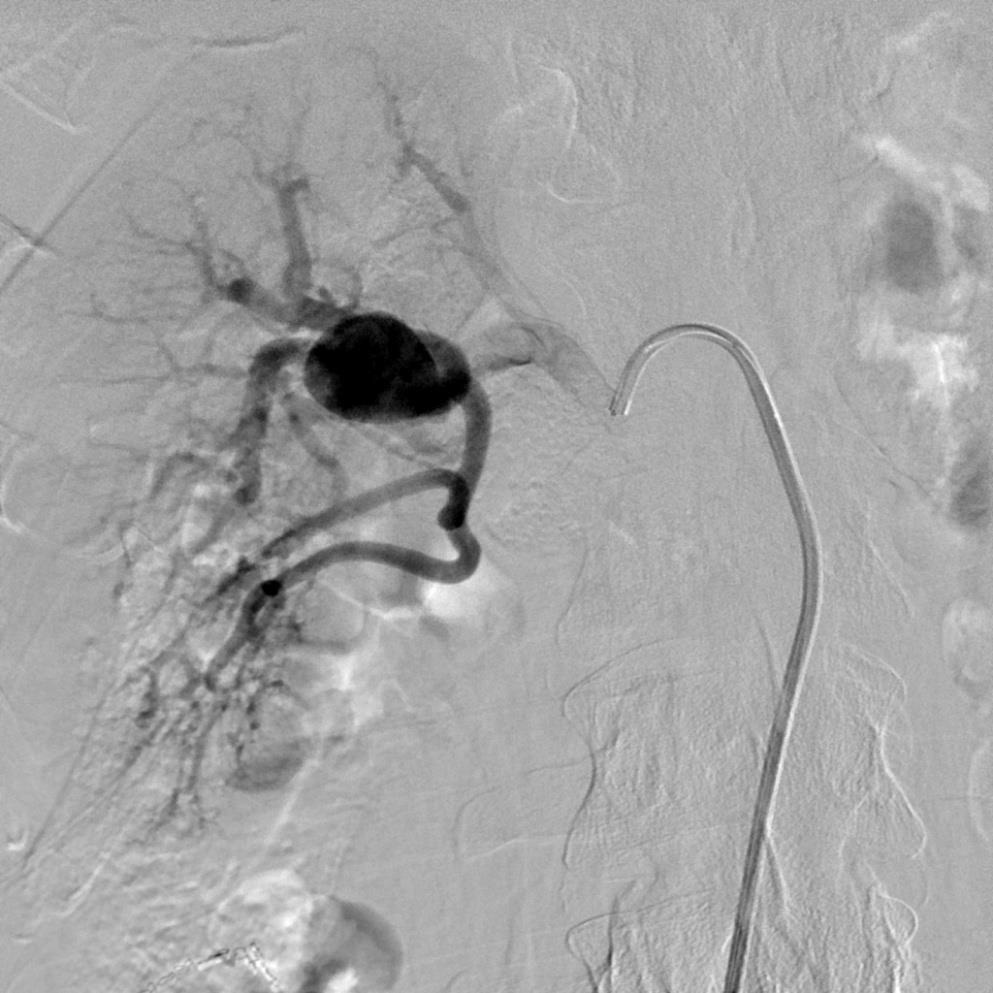

54岁,女性,提示有肾动脉瘤。尽管动脉造影可能为窄颈动脉瘤,但不能显示清晰的工作位(Working Position)。工作位是指能够清晰显示动脉瘤颈与载瘤动脉的切线位,以便在填塞微弹簧圈的时候可以清晰地观察弹簧圈封堵瘤颈的情况,避免栓塞不足或过度栓塞导致载瘤动脉的闭塞。DSA情况下,如果这种关系为前后或后前位的情况下是不能够被清晰地显示。

微导丝进入动脉瘤颈的远端

设计用于颅内动脉瘤支撑架跨瘤颈放置

支撑架完全释放后显示动脉瘤仍然显影